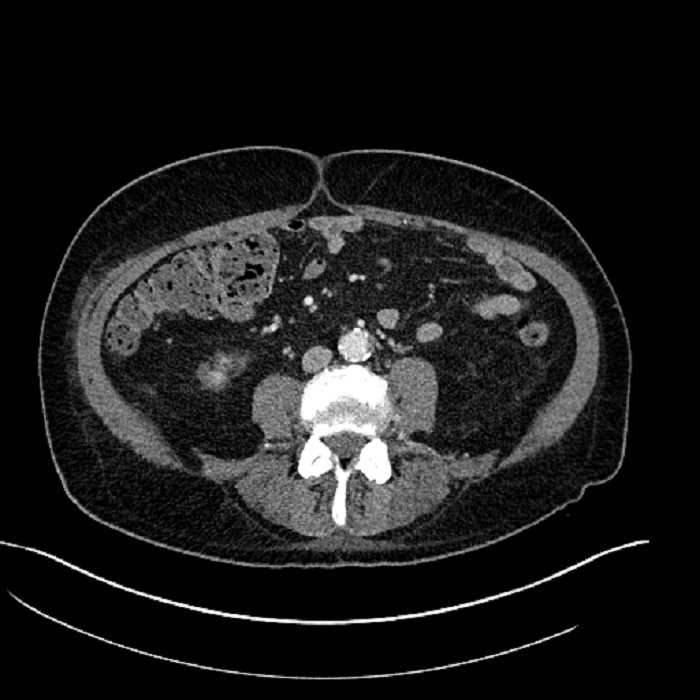

Age: 63

Sex: Male

Indication: Abdominal pain

• Large fluid density structure in hepatic segments 7 and 8 measuring 10 x 7 x 7 cm with internal septation and circumferential ill-defined low density compatible with edema

• Peripherally enhancing subcapsular collections along the anterior margin of the left hepatic lobe measuring 3 x 1 cm and 2 x 1 cm

• Clearly marginated fluid density structure in segment 7 and several other scattered tiny hypodensities, which likely represent cysts

• Mild mural thickening of a segment of the sigmoid colon with adjacent fat stranding and a 1.5 cm fluid and gas collection along the tip of an inflamed diverticulum

• Loss of the normal fat plane between this collection and adjacent loops of small bowel, which demonstrate mural thickening

Acute sigmoid diverticulitis complicated by a small contained perforation and a large abscess in the right hepatic lobe. Additional small subcapsular abscesses along the anterior margin of the left hepatic lobe.

Additionally, loss of the normal fat plane between the peridiverticular collection and adjacent thickened loops of small bowel raises the potential for an enterocolonic fistula.

• The classic CT imaging appearance is a double target sign with internal low density surrounded by an internal enhancing rim (capsule) and a low density external rim (edema)

Hepatic abscess showing the double target sign with low density internally surrounded by a thin inner enhancing rim (red arrow) and ill-defined outer low density rim (yellow arrow). Blue arrow indicates an internal septation. Red arrows: additional smaller subcapsular abscesses. Red arrow: focal contained perforation associated with diverticulitis.